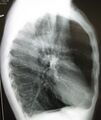

A chest X-ray is not useful to establish a diagnosis of COPD but it is of use in either excluding other conditions or including comorbidities such as pulmonary fibrosis and bronchiectasis. Characteristic signs of COPD on X-ray include hyperinflation (shown by a flattened diaphragm and an increased retrosternal air space) and lung hyperlucency.[5] A saber-sheath trachea may also be shown that is indicative of COPD.[110]

A lateral chest X-ray of a person with emphysema, displaying barrel chest and flat diaphragm